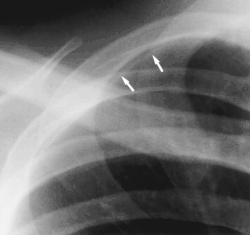

- Clavicular companion shadow is a thin soft-tissue stripe along the upper edge of the clavicle.[1]

- Scapular companion shadow overlie the scapula, with a smooth, well-defined margin parallel to the medial border of the scapula. The companion shadow results from unusual radiographic position of the scapula, which causes a soft-tissue fold to occur along its medial border. Winging of the scapula may also be responsible for the shadow. Scapular companion shadows may be mistaken for a soft-tissue or pleural lesion.[3]